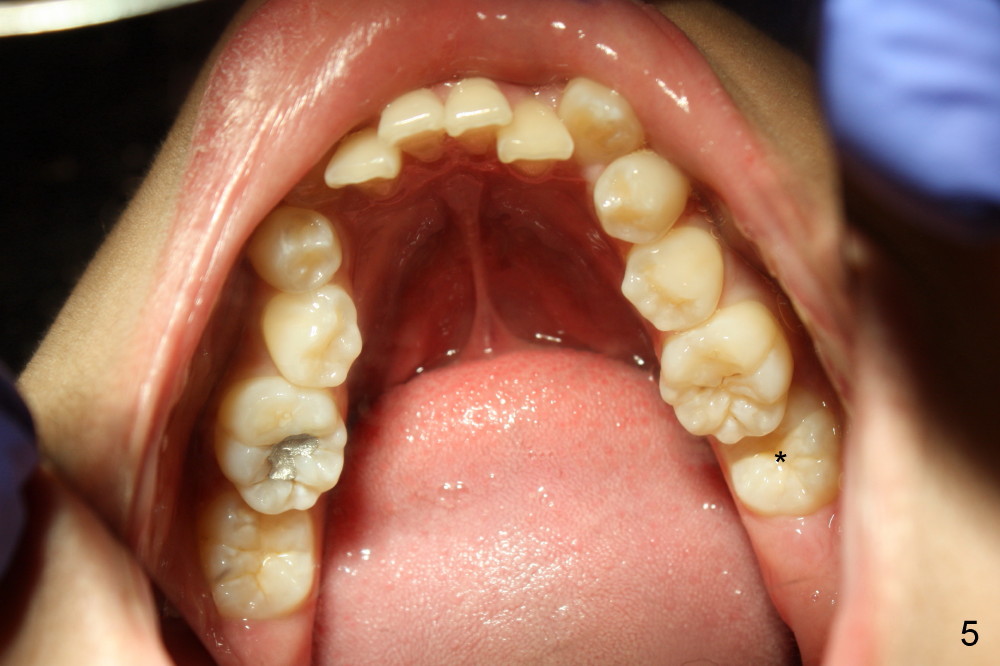

A 13-year-old boy has severe crowding (Fig.1-5). Four of the first bicuspids were extracted on 02/17/2014. Full mouth brackets or bands (except #18) were placed on 03/27/2014. Alignment improved 2 months later (Fig.11, 05/24/2014). The upper 18 ss wire was modified (Fig.12), and fixed with alastiks (Fig.13,14). One month later (07/01/2014), local alignment also improved (Fig.15); the upper modification is confined to one tooth.